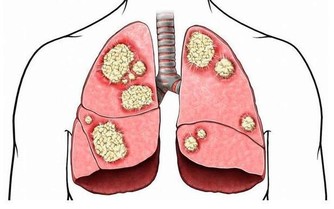

醫學上,胰腺癌是一種惡性程度很高,診斷和治療都很困難的消化道惡性腫瘤,約90%為起源於腺管上皮的導管腺癌。其發病率和死亡率近年來明顯上升。5年生存率<1%,是預後最差的惡性腫瘤之一,正因如此,人們將其稱為癌症之王!胰腺癌早期的確診率不高,手術死亡率較高,而治愈率很低。本病發病率男性高於女性,男女之比為1.5~2:1,男性患者遠較絕經前的婦女多見,絕經後婦女的發病率與男性相仿。

胰腺癌的病因尚不十分清楚。但大量的流行病學數據顯示,它的發生與吸煙、飲酒、高脂肪和高蛋白飲食、過量飲用咖啡、環境污染及遺傳因素有關;近年來的調查報告發現糖尿病人群中胰腺癌的發病率明顯高於普通人群;也有人注意到慢性胰腺炎病人與胰腺癌的發病存在一定關係,發現慢性胰腺炎病人發生胰腺癌的比例明顯增高;另外還有許多因素與此病的發生有一定關係,如職業、環境、地理等。

其實胰腺癌早期症狀非常隱匿,可能只是輕微的腹痛腹脹,很多患者常常把胰痛當做胃痛,直到出現很嚴重的症狀時,才會來醫院就診,可是往往已喪失手術機會。

一般未接受治療的胰腺癌病人的生存期約為4個月,接受旁路手術治療的病人生存期約7個月,切除手術後病人一般能生存16個月。但普遍預後較差,而像小侯這種情況,因為發現的時候,癌細胞已經全身轉移,所以,他的生存期不會超過半年,命運多舛,現在癌症的發病率越來越年輕,我們提醒各位,一定要養成良好的生活方式,避免悲劇重演!